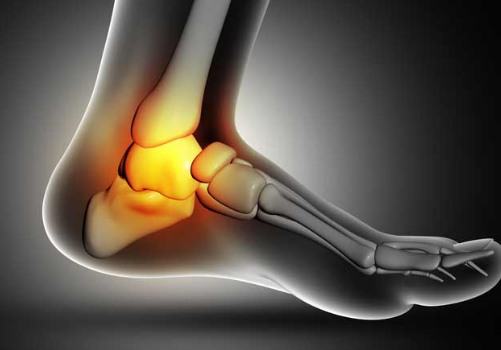

발목 통증?

발목 통증은 발목관절에 느껴지는 불편감이나 통증을 말합니다. 경증부터 중증까지 다양하며 갑자기 발생하거나 시간이 지남에 따라 점진적으로 발생할 수 있습니다. 발목 통증은 한쪽 또는 양쪽 발목에 영향을 미칠 수 있으며 다양한 요인에 의해 발생할 수 있습니다.